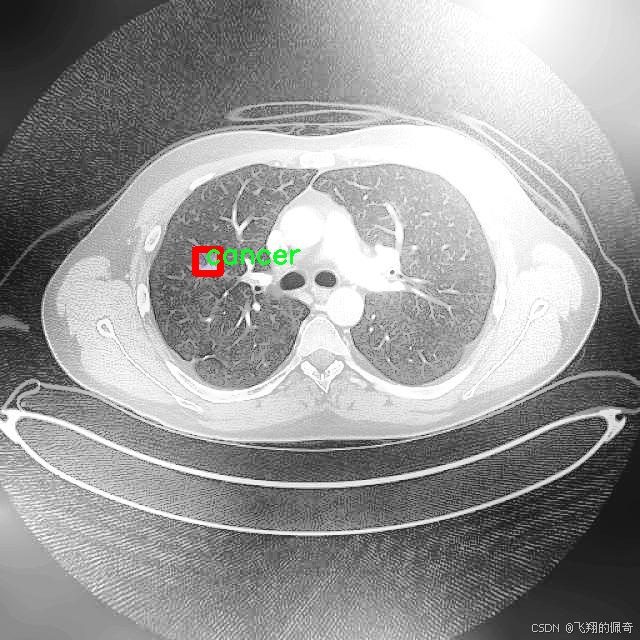

本研究将基于改进的YOLOv8模型,构建一个高效的肺结节图像分割系统。所使用的数据集包含1600幅图像,涵盖了三类重要的病理类型:腺癌、癌症和结节。这些数据不仅为模型的训练提供了丰富的样本,也为后续的模型评估和验证奠定了基础。通过对不同类别的肺结节进行精确分割,研究旨在提高模型在实际应用中的鲁棒性和准确性,进而为临床医生提供更为可靠的辅助诊断工具。

图片效果

在肺结节图像分割的研究中,数据集的选择与构建至关重要。本研究所采用的数据集名为“Lung Nodule Segmentation study”,其设计旨在为改进YOLOv8-seg模型提供高质量的训练数据。该数据集专注于肺部影像中的结节分割,特别是针对不同类型的肺结节进行精确标注,以便于后续的深度学习模型训练和性能评估。

“Lung Nodule Segmentation study”数据集中包含三种主要类别,分别为腺癌(adenocarcinoma)、癌症(cancer)和结节(nodule)。这些类别的选择不仅反映了肺部影像学中的常见病理类型,也为模型的多样性和适应性提供了基础。腺癌作为一种常见的肺癌类型,其在影像学上的表现与其他类型的肺结节有显著差异,因此在数据集中占据了重要地位。癌症这一类别则涵盖了更广泛的病理变化,旨在提高模型对不同癌症类型的识别能力。结节类别则是数据集的核心,主要用于训练模型在图像中准确识别和分割出肺结节的区域。